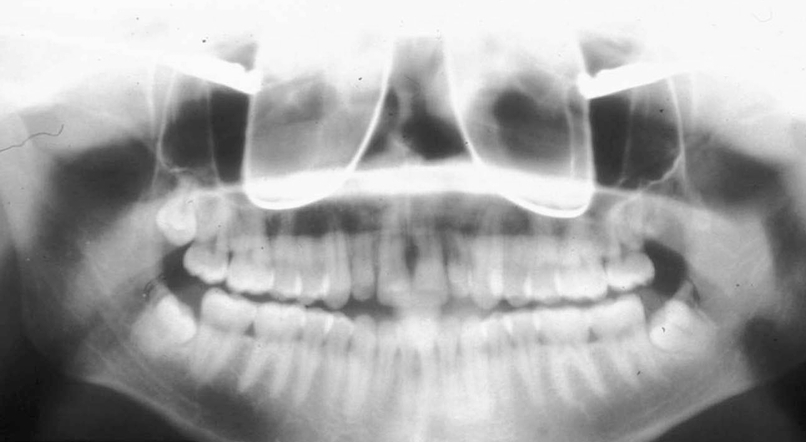

Q

What is wrong with this image?

A

Inferior turbinates and meati spread across maxillary sinuses (too far back)

(also ghost image of earrings?-haley)